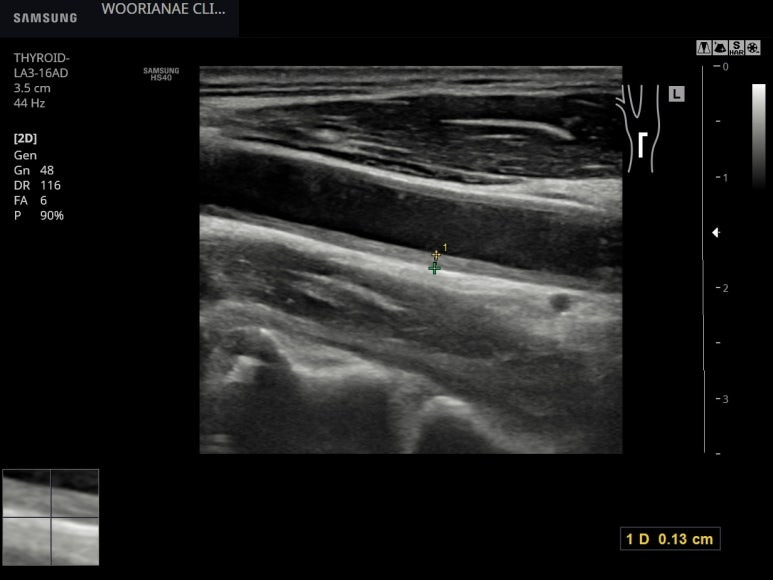

같은 맥락에서 복부 초음파시 우측 장골동맥에 경화반이 관찰되었다.